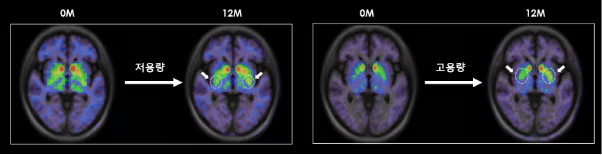

S.BIOMEDICS利用TED-A9治疗帕金森病的多巴胺细胞疗法在I/IIa期临床试验中取得了12个月的良好效果

根据S.Biomedics公司本月初在奥地利维也纳举行的国际会议上公布的研究结果,低剂量和高剂量治疗组患者的运动功能评分较植入前均提高了高达28.9%。低剂量和高剂量组患者的精神和情绪症状以及自主神经症状也均得到显著改善。

低剂量和高剂量TED-A9植入一年后的脑成像。

尤其是在干细胞治疗帕金森病植入一年后,对脑成像图像进行分析后发现,多巴胺转运蛋白的表达较植入前有所增加。干细胞治疗的开发者、延世大学医学院金东旭教授指出:“这表明干细胞在脑内存活,成熟为多巴胺神经细胞,并与周围区域和突触(神经细胞之间的连接)形成整合。”他补充道:“这可以被视为帕金森病中替换死亡多巴胺神经细胞的根本治疗机制的有力证据。”